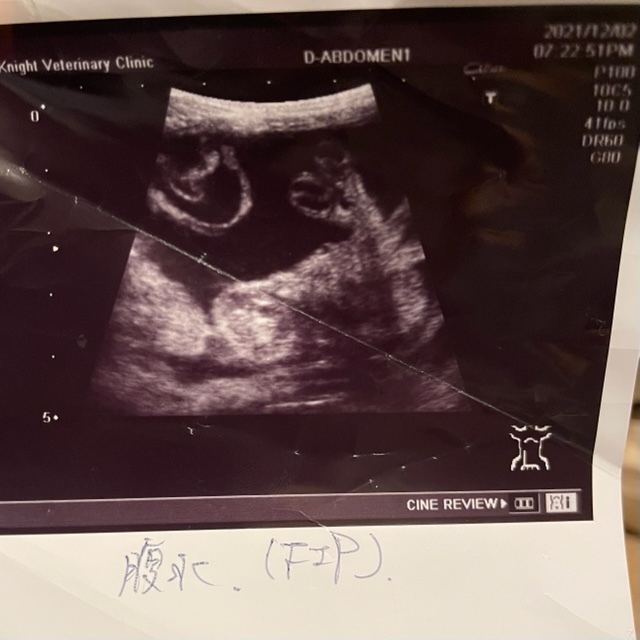

お腹が膨れている原因は寄生虫か腹水がたまっているということで、超音波検査したところ、寄生虫であると診断されました。

12/2 腹水が溜まっておりFIP(猫伝染性腹膜炎)の疑いがあると言われ血液検査をする

12/4 今にも破裂しそうなくらい腹水でお腹がカンカンになっていたため再度受診し腹水を抜いて頂く

その時に恐らくFIPの可能性が高いと診断され、FIPの治療を行っている動物病院で治療の流れを聞いておいた方がいいと獣医さんに勧められる。

たくさんのFIPの猫ちゃんを診られている獣医さんが「検査結果を見なくても慢性的な下痢、発熱、腹水の症状から診てFIPで間違いない」と宣言される。